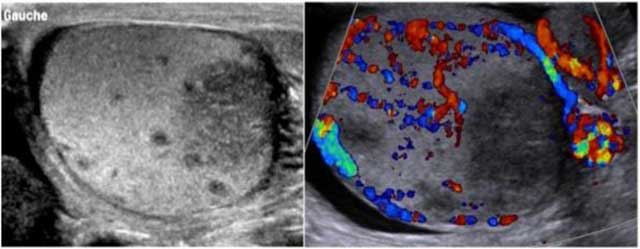

Figure 1

Grayscale and color Doppler of the left testis demonstrate hypoechoic avascular area of the hilum; the remaining testicular and epididymal parenchyma are more hyperechoic with flow detection.